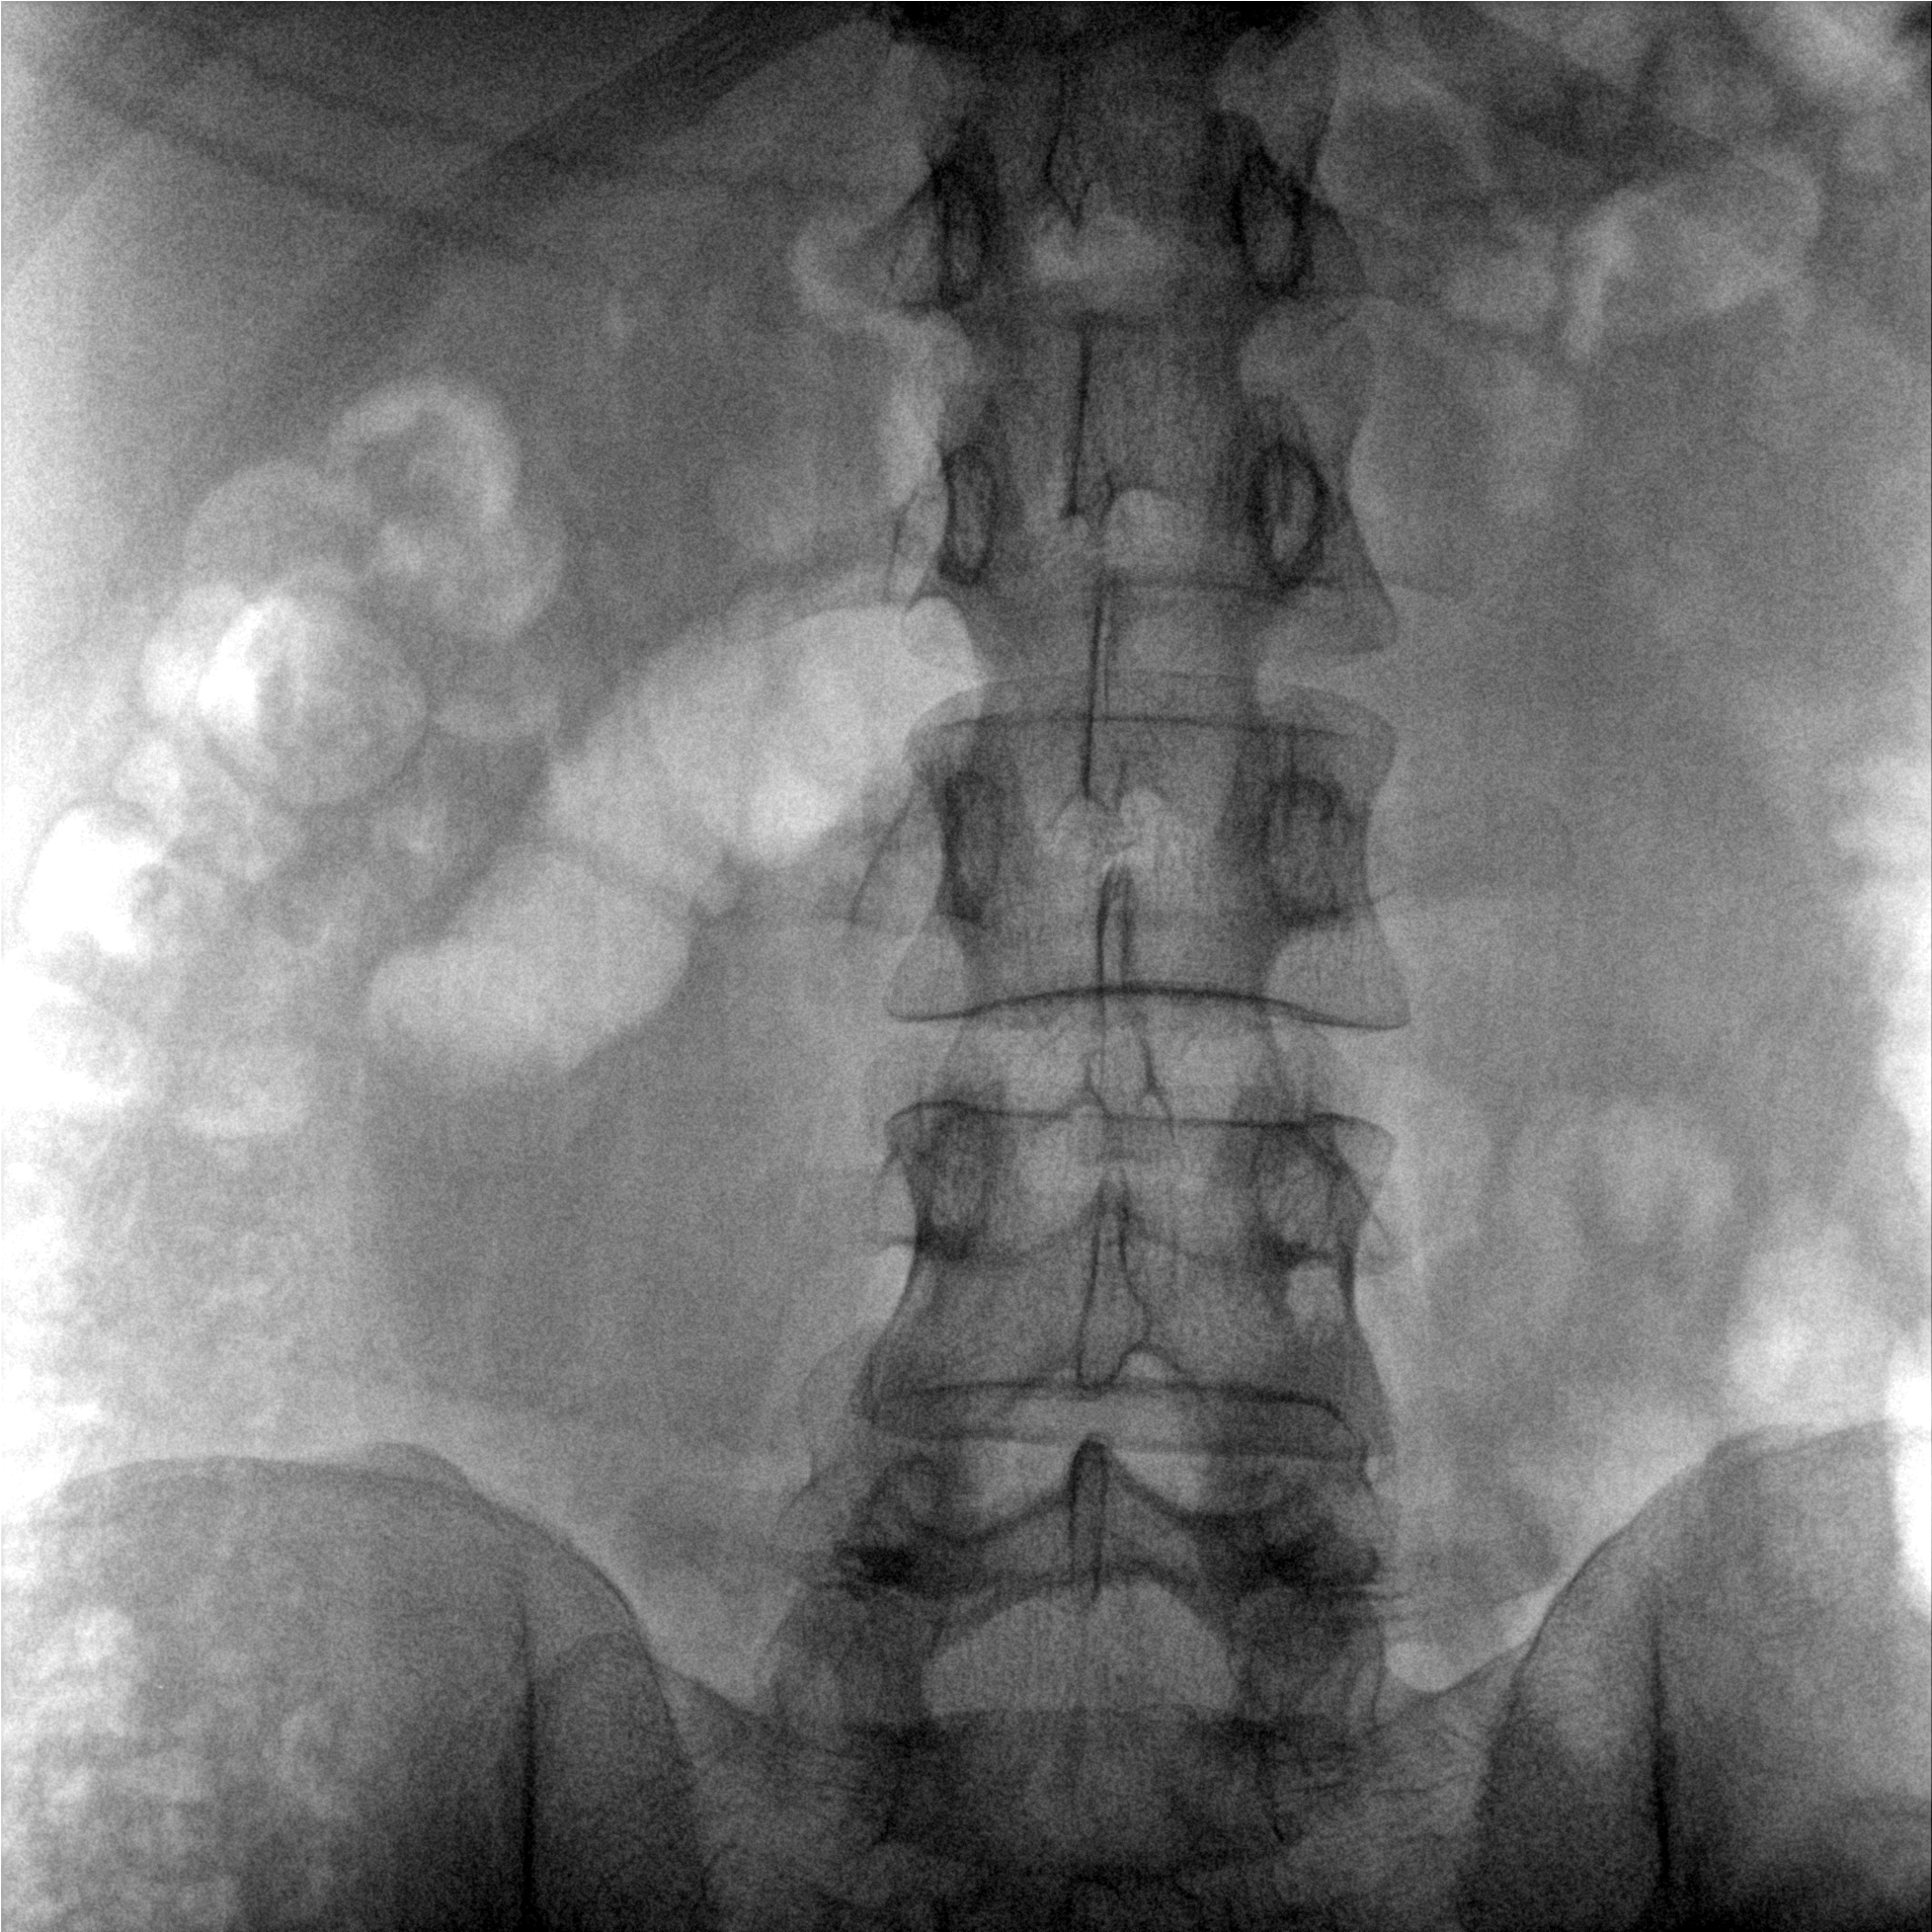

成像清晰、操作簡(jiǎn)易、擺位便捷,主要適用于骨科、脊柱外科、矯形外科、創(chuàng)傷骨科及手術(shù)室等,能大幅度提升手術(shù)水準(zhǔn),降低手術(shù)風(fēng)險(xiǎn)和并發(fā)癥的概率。

提供更大的術(shù)中三維成像視野,采集更多圖像信息,可一次拍全全段頸椎、全段腰椎、七節(jié)胸椎、雙側(cè)骶髂關(guān)節(jié)、股骨頭及單側(cè)盆骨。